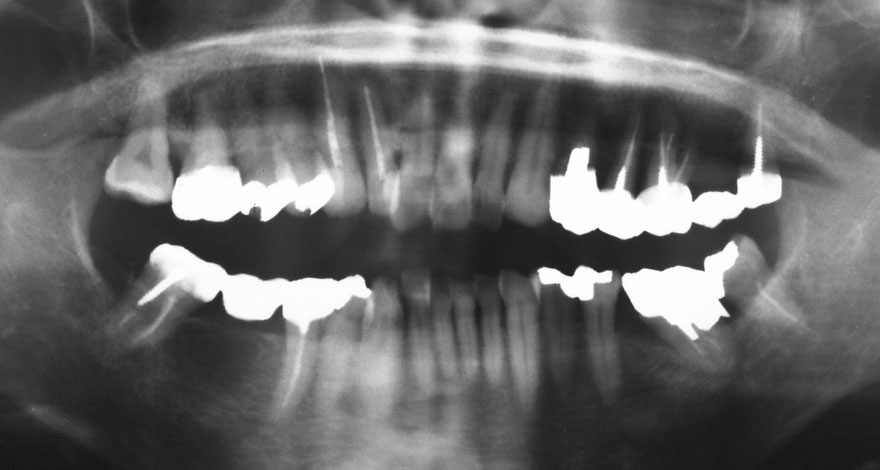

初診時 39歳 女性 平均歯槽骨喪失量:1.82mm

29年後 68歳

平均歯槽骨喪失量:2.21mm

29年間喪失量:-0.39mm

年間喪失速度:-0.013mm

(ケア頻度:5.55ヵ月ごと)